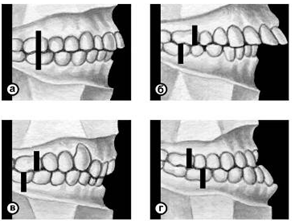

Различают несколько вариантов нормального П. (ортогнатический, прогенический, прямой, бипрогнатический). Они характеризуются смыканием зубных рядов на всем протяжении и отличаются друг от друга лишь особенностями смыкания функционально ориентированных групп зубов, в частности передних. Эталонным принято считать ортогнатический прикус (рис. 5, а), при котором верхний зубной ряд на всем протяжении перекрывает нижний, а во фронтальном участке верхние резцы перекрывают нижние не более чем на 1/3 коронковой части зуба; между резцами верхней и нижней челюстей имеется режуще-бугорковый контакт. Прогенический прикус (рис. 5, б) отличается умеренным выстоянием нижнего зубного ряда. Прямой прикус (рис. 5, в) характеризуется тем, что верхние резцы не перекрывают нижние, а смыкаются режущими краями. При бипрогнатическом прикусе (рис. 5, г) верхние и нижние резцы наклонены в сторону преддверия рта, но между ними сохранен режуще-бугорковый контакт. Для всех вариантов нормального прикуса обязательным условием является нормальное функционирование зубочелюстной системы.

Рис. 5а). Схематическое изображение челюстей при основных разновидностях нормального прикуса (вид сбоку): ортогнатический прикус.

Рис. 5б). Схематическое изображение челюстей при основных разновидностях нормального прикуса (вид сбоку): прогенический прикус.

Рис. 5в). Схематическое изображение челюстей при основных разновидностях нормального прикуса (вид сбоку): прямой прикус.

Рис. 5г). Схематическое изображение челюстей при основных разновидностях нормального прикуса (вид сбоку): бипрогнатический прикус.